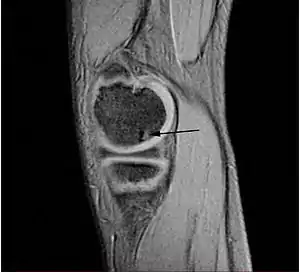

![]() Lesión típica de osteocondritis disecante en la cabeza del fémur, causada por una necrosis avascular del tejido subcondral. | ||